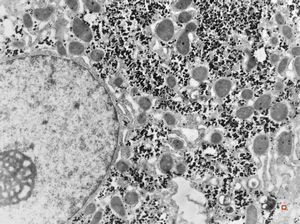

F,33y. | "ground glass" hepatocyte … filamentous inclusions ofhepatitis B surface antigen(HBsA)